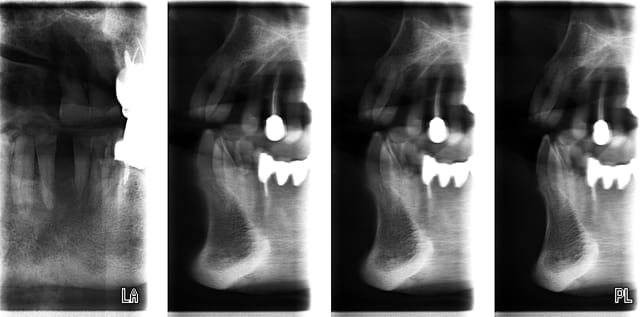

pour ceux qui en ont assez d'envoyer leur patients se faire faire un scanner et d'attendre le retour dudit patient, la solution peut s'appeller pro max;

comme son prix en version 3D m'inquiétait un peu, (+ de 100.000 €), je l'ai acheté en version allégée, sans la 3D; elle fait donc les panos et surtout les tomos (voir fichiers ci joint); les résultats sont assez intéressants; la version 3D sera ajoutée dans un an ou deux; je pense que ça ne peut pas remplacer à 100 % un scanner pour préparer un soulevé de sinus par abord latéral, mais ça le fait très bien pour le reste; pour les sinus par abord crestal, j'attend de voir

J'ai travaillé dans un cabinet d'implanto qui l'avait, le praticien en avait l'air content, mais les clichés tomos étaient très inégaux et devaient souvent être recommencés (bonjour l'irradiation), pour un résultat quand même souvent assez "impressionniste". Il est quand même assez fréquent que sur les quatre coupes, une seule "coupe" vraiment quelquechose.

Je pense que c'est plus utile pour avoir une "idée" de l'anatomie, plutôt que pour faire quelque chose de précis.

pour les résultats "impressionnistes", que penses tu des fichiers en pièces jointes?

je viens de faire une pano pour contrôler un soulevé tout à l'heure, je le post en PJ car je trouve la définition extra, et il n'y a pas de déformation : l'implant est rectiligne, contrairement à ceux sur la dernière pano que j'ai reçue d'un radiologue il y a 15 jours qui étaient déformés; en plus , le biomat' n'était pas très bien visible, là, il est super

le liseré foncé autour de l'implant est normal, il n'existe pas sur une rétro